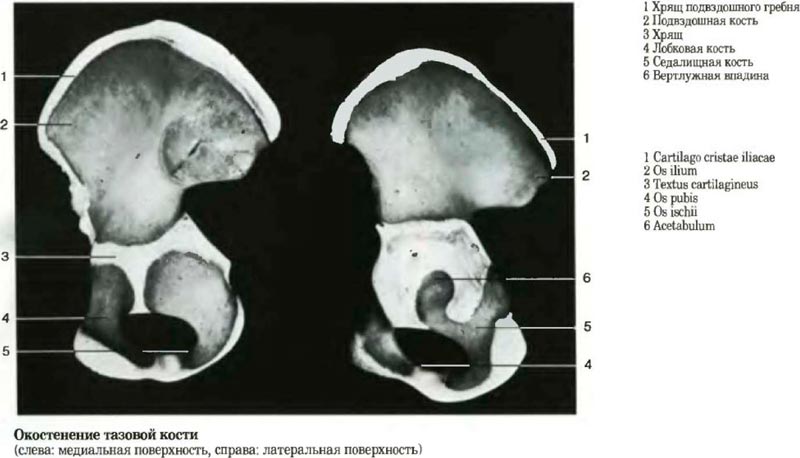

Окостенение тазовой кости |

|||